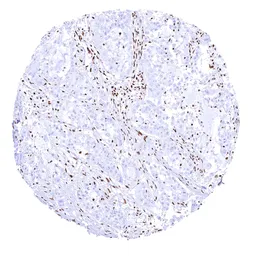

Anti-BRG1 antibody [MSVA-397R] HistoMAX™ used in IHC (Paraffin sections) (IHC-P). GTX04486